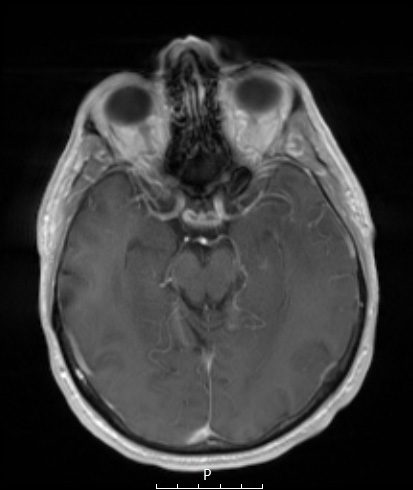

A T1-weighted image showed hypointensity in the same area with contrast which failed to enhance.